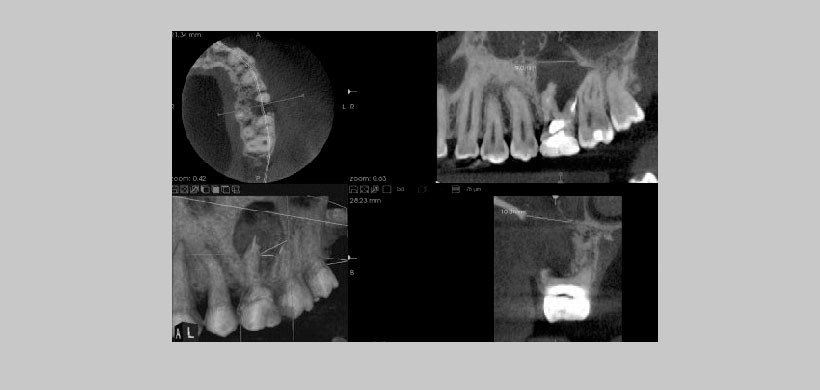

Fig 2. Se observa en corte sagital la extensión de la lesión apical y la proximidad y pérdida de la integridad del piso sinusal. Se puede observar además, la medición en milímetros de la perforación del piso de seno maxilar, posibilidad que permite este tipo de estudio por imágenes. En imagen de volumen rendering se observa la dimensión y localización de la lesión apical.